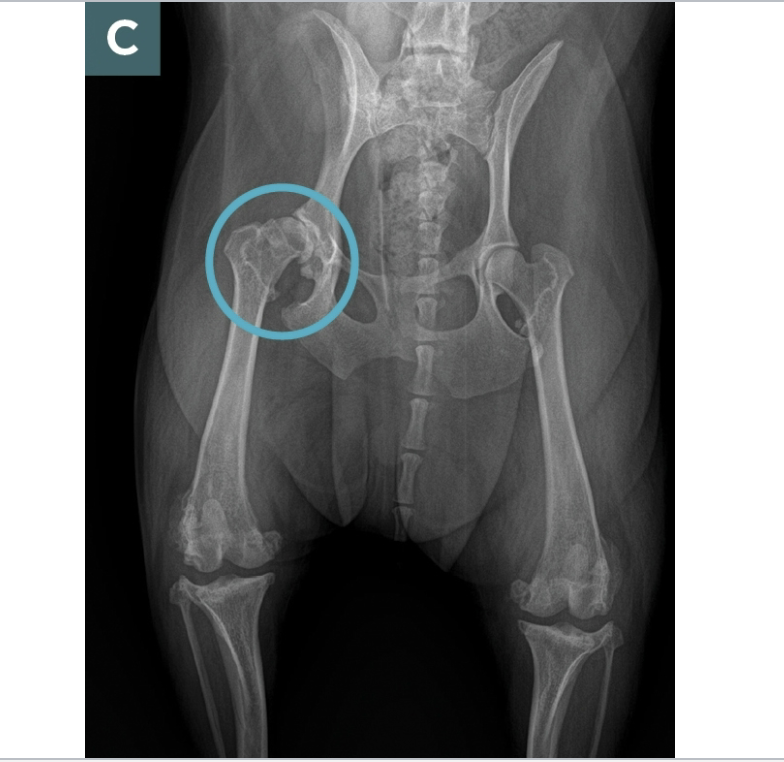

HD what does it look like of radiographs

Flattened femoral head

Thickened femoral neck

Shallow/ sclerotic acetabulum

Numerous osteophytes

What are some signs of arthritic changes

Acetabulum is almost not visible

Bone spurs above hip joints

Thickening and remodeling of the femoral head